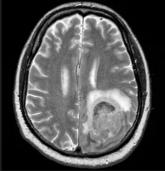

NMO: Study says double diagnoses with MS are common

Nearly half of patients with coding for NMO were also listed as having MS – a very similar condition.

Two MS researchers disagree over how tightly they’re connected, and one says “second hit” may be factor.